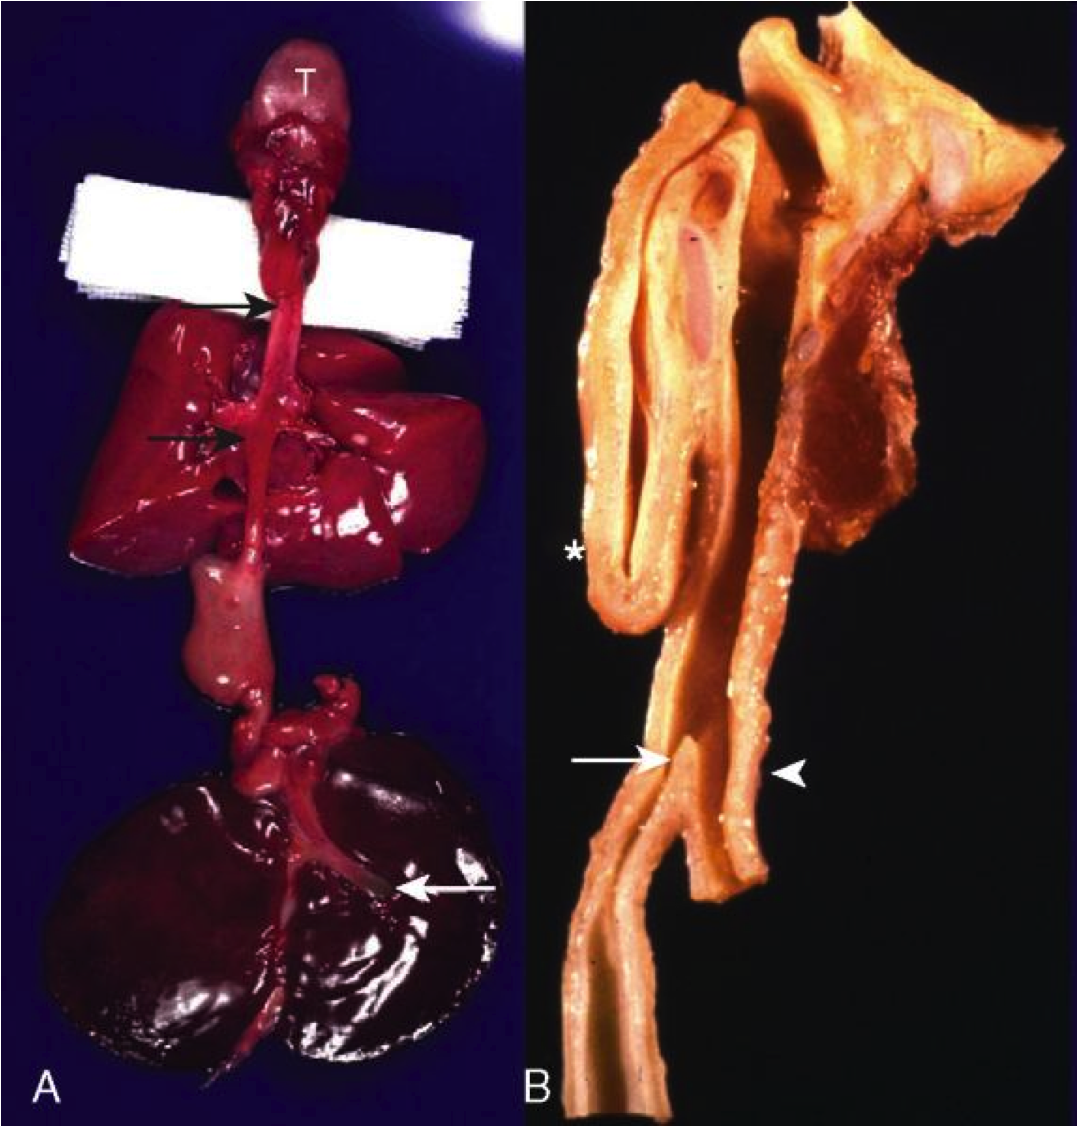

Esophageal diverticula

Outpouchings of the esophageal wall

- True = all layers, including muscle

- False = mucosa & submucosa only

- Zenker’s diverticulum = false, cervical esophagus, elderly (motor dysfx)

- Epiphrenic diverticulum = true, any age, just above diaphragm

Reflect underlying motor dysfunction

image=Zenker’s diverticulum